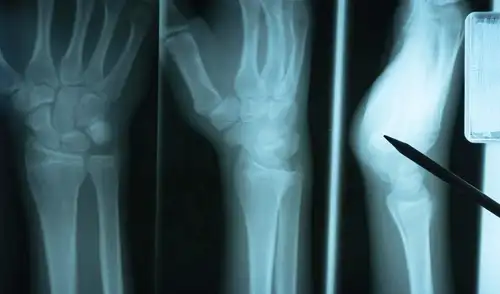

Un estudio titulado “APEX1, a transcriptional hub for endochondral ossification and fracture repair”, publicado en la revista científica Bone Research, identificó un mecanismo celular clave que influye directamente en la consolidación de fracturas y en el riesgo de pseudoartrosis, una complicación que impide la correcta unión de los huesos. La investigación, centrada en la proteína APEX1 y su papel en la reparación ósea, revela que el equilibrio de ciertas señales químicas dentro de las células es determinante para una recuperación eficaz.

El estudio identificó a la proteína como un regulador central en la respuesta celular durante la reparación de fracturas. Esta molécula participa en la detección y corrección de daños en el ADN, además de intervenir en la señalización intracelular vinculada al estrés oxidativo. Su actividad permite que las células óseas respondan de manera adecuada a las condiciones generadas tras una lesión.

Los investigadores observaron que una regulación deficiente altera la comunicación molecular necesaria para activar los mecanismos de reconstrucción. Esta disfunción puede retrasar la formación de nuevo tejido y aumentar la probabilidad de pseudoartrosis, una condición que afecta la estabilidad estructural del hueso y prolonga el tiempo de recuperación.

El trabajo también destaca que el nivel controlado de ROS es esencial para iniciar la cascada de eventos que conducen a la regeneración. Estas moléculas activan proteínas específicas que promueven la proliferación y diferenciación de células responsables de formar nuevo tejido óseo. Sin esta señalización, el proceso de reparación pierde eficacia.

Los resultados aportan una nueva perspectiva sobre los factores biológicos que determinan el éxito o fracaso de la consolidación ósea. Comprender el rol de APEX1 y las señales oxidativas abre la posibilidad de desarrollar tratamientos dirigidos a mejorar la recuperación de fracturas, especialmente en pacientes con riesgo elevado de complicaciones o con procesos de cicatrización deficientes.